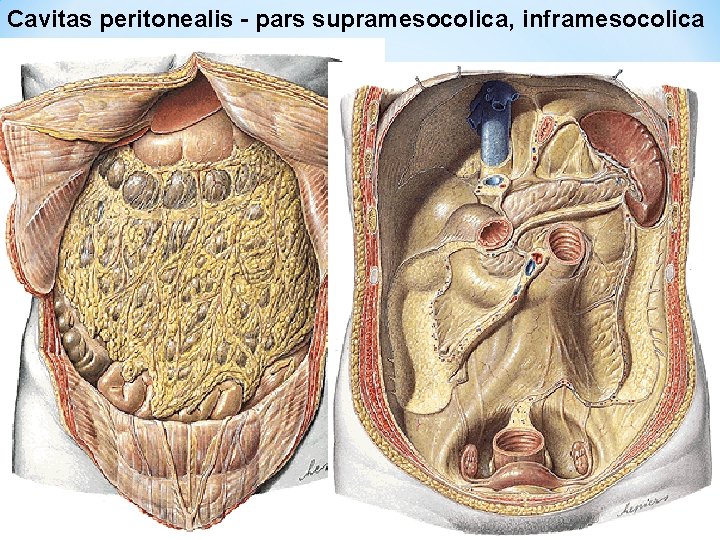

Cavitas peritonealis - pars supramesocolica, inframesocolica